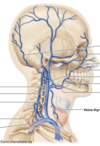

vascularisation du membre supérieur, thorax et abdomen Flashcards